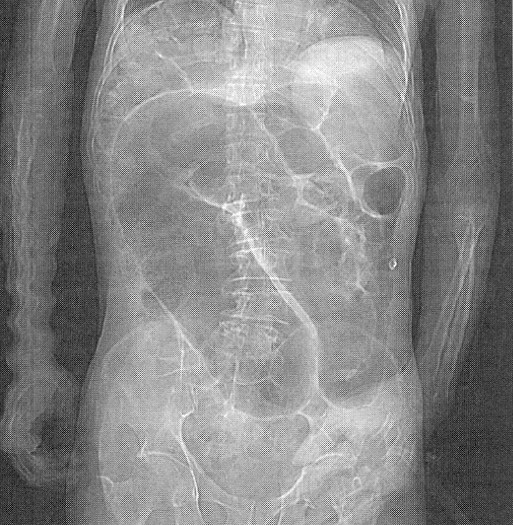

In the presented case, the abdominal film shows a markedly dilated bowel (megacolon)

and the EKG shows a supraventricular tachycardia (300 beats/minute) and biventricular

heart block.